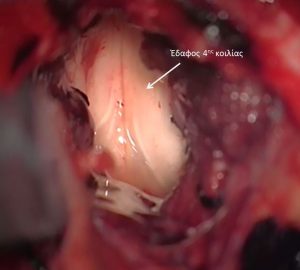

Τα επενδυμώματα ανήκουν στα γλοιώματα και αναπτύσσονται τυπικά εντός ή πλησίον του επενδύματος του κοιλιακού συστήματος του εγκεφάλου. Η πιο συνηθισμένη θέση είναι η περιοχή της παρεγκεφαλίδας (Εικόνα 1 & 2).